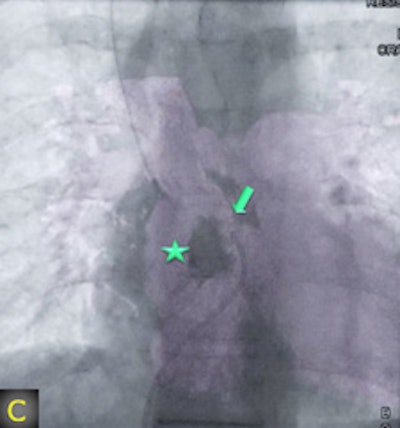

"The fusion of 3D reconstructions with live fluoroscopic images during catheterization may help to find the ideal fluoroscopic angulation during catheter-based interventions, to achieve difficult vascular crossings by the wire or the catheter, to choose the most appropriate material for catheterization, and to define and control optimized positioning of implants such as stents or valve prostheses," Glöckler and colleagues explained.

"One unique feature of FD-CT is the possibility of merging 3D reconstructions with the real-time fluoroscopic image," a potentially useful way to identify ideal C-arm angulations for achieving wire passage for atypical vascular crossings, and to optimally depict the implant position of coils, plugs, stents, and valves," Glöckler and colleagues wrote. "In fact, image fusion of 3D reconstructed FD-CT images with the live fluoroscopic image was frequently rated as 'very useful' (57.4%)."

A typical example is the visualization of the coronary arteries during transcatheter pulmonary valve implantation.